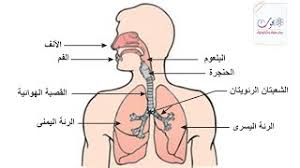

اعضاء جهاز التنفس

الانف

البلعوم

الحنجرة

القصبة الهوائية

الرئتين

الحجاب الحاجز

الاضلاع